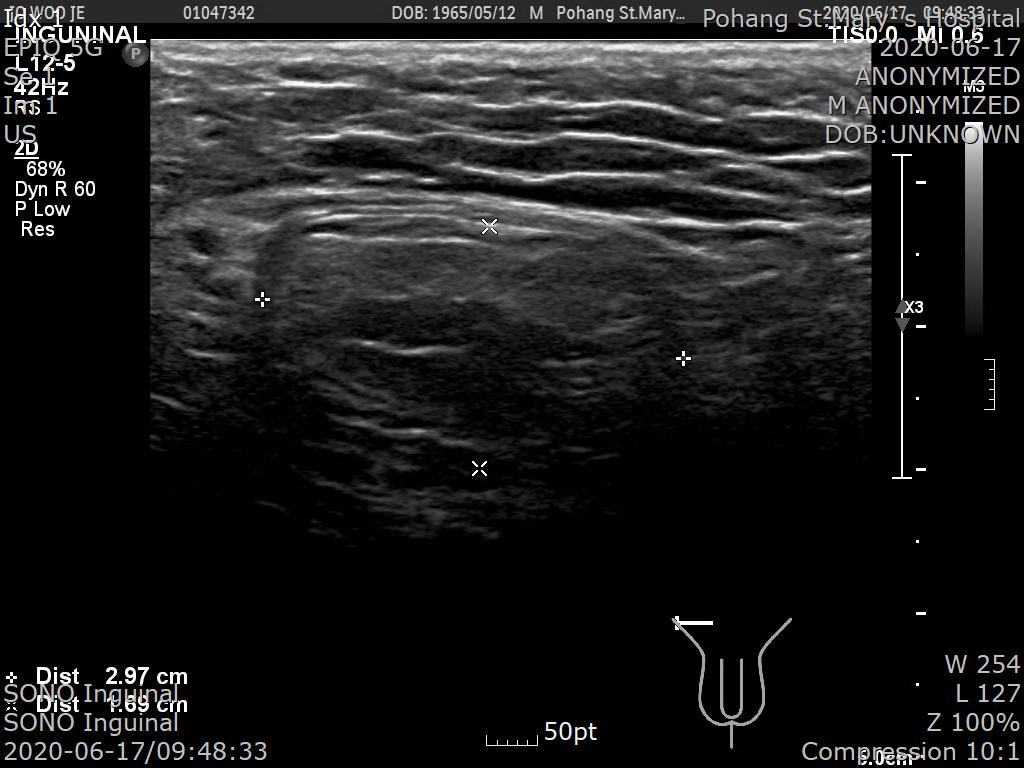

서혜부 초음파를 시행했습니다.

[초음파 판독 소견]

▶SONO Inguinal

1. Direct inguinal hernia of omental fat, right

2. Negative finding in left inguinal area

초음파 소견상 복강경 수술했던 좌측 서혜부탈장은 재발소견 없이 깨끗하며 우측 불룩한 덩어리는 직접 서혜부 탈장으로 진단되었습니다.